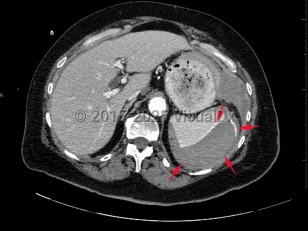

The American Association for the Surgery of Trauma (AAST) has a spleen injury grading system based on imaging and intraoperative findings:

- Grade I: subcapsular hematoma < 10% of surface area; capsular tear; parenchymal laceration < 1 cm depth.

- Grade II: subcapsular hematoma 10%-50% of surface area; parenchymal laceration 1-3 cm in depth that does not involve a trabecular vessel.

- Grade III: subcapsular hematoma > 50% of surface area or expanding ruptured subcapsular or intraparenchymal hematoma; intraparenchymal hematoma > 5 cm in diameter or expanding; parenchymal laceration > 3 cm in depth or involving trabecular vessels.

- Grade IV: laceration involving segmental or hilar vessels producing major devascularization (> 25% of spleen). Grade V: completely shattered spleen; hilar vascular injury devascularizes spleen.